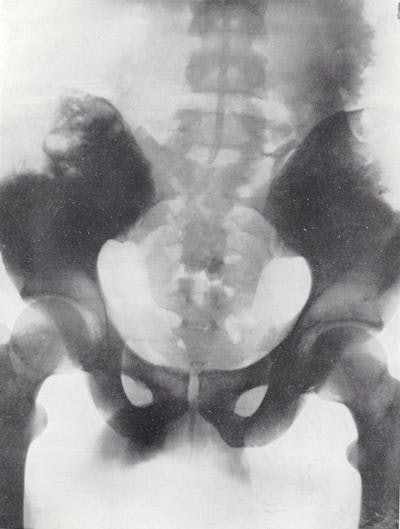

This new device was marketed as the Potter-Bucky diaphragm and was announced in February 1917 at the ARRS.4 Potter demonstrated the use of this apparatus to show the lumbar spine, hips and pelvis, and renal calculi. It is famously recorded that at one meeting after Potter had shown his work, one radiologist was so surprised by the quality of the images that he accused Potter of touching up the negatives!

There was a certain delay in making the apparatus commercially available because of discussions about the priority of the discovery. However, in 1921 the Potter-Bucky diaphragm was finally marketed and was immediately accepted by the radiological profession. Whilst the image of the pelvis from 1921 is excellent, it should be noted that the exposure time was 12 seconds!

Normal pelvis from 1921 using the Potter-Bucky diaphragm and a Coolidge tube.Dr. Adrian Thomas is chairman of the International Society for the History of Radiology and honorary librarian at the British Institute of Radiology.